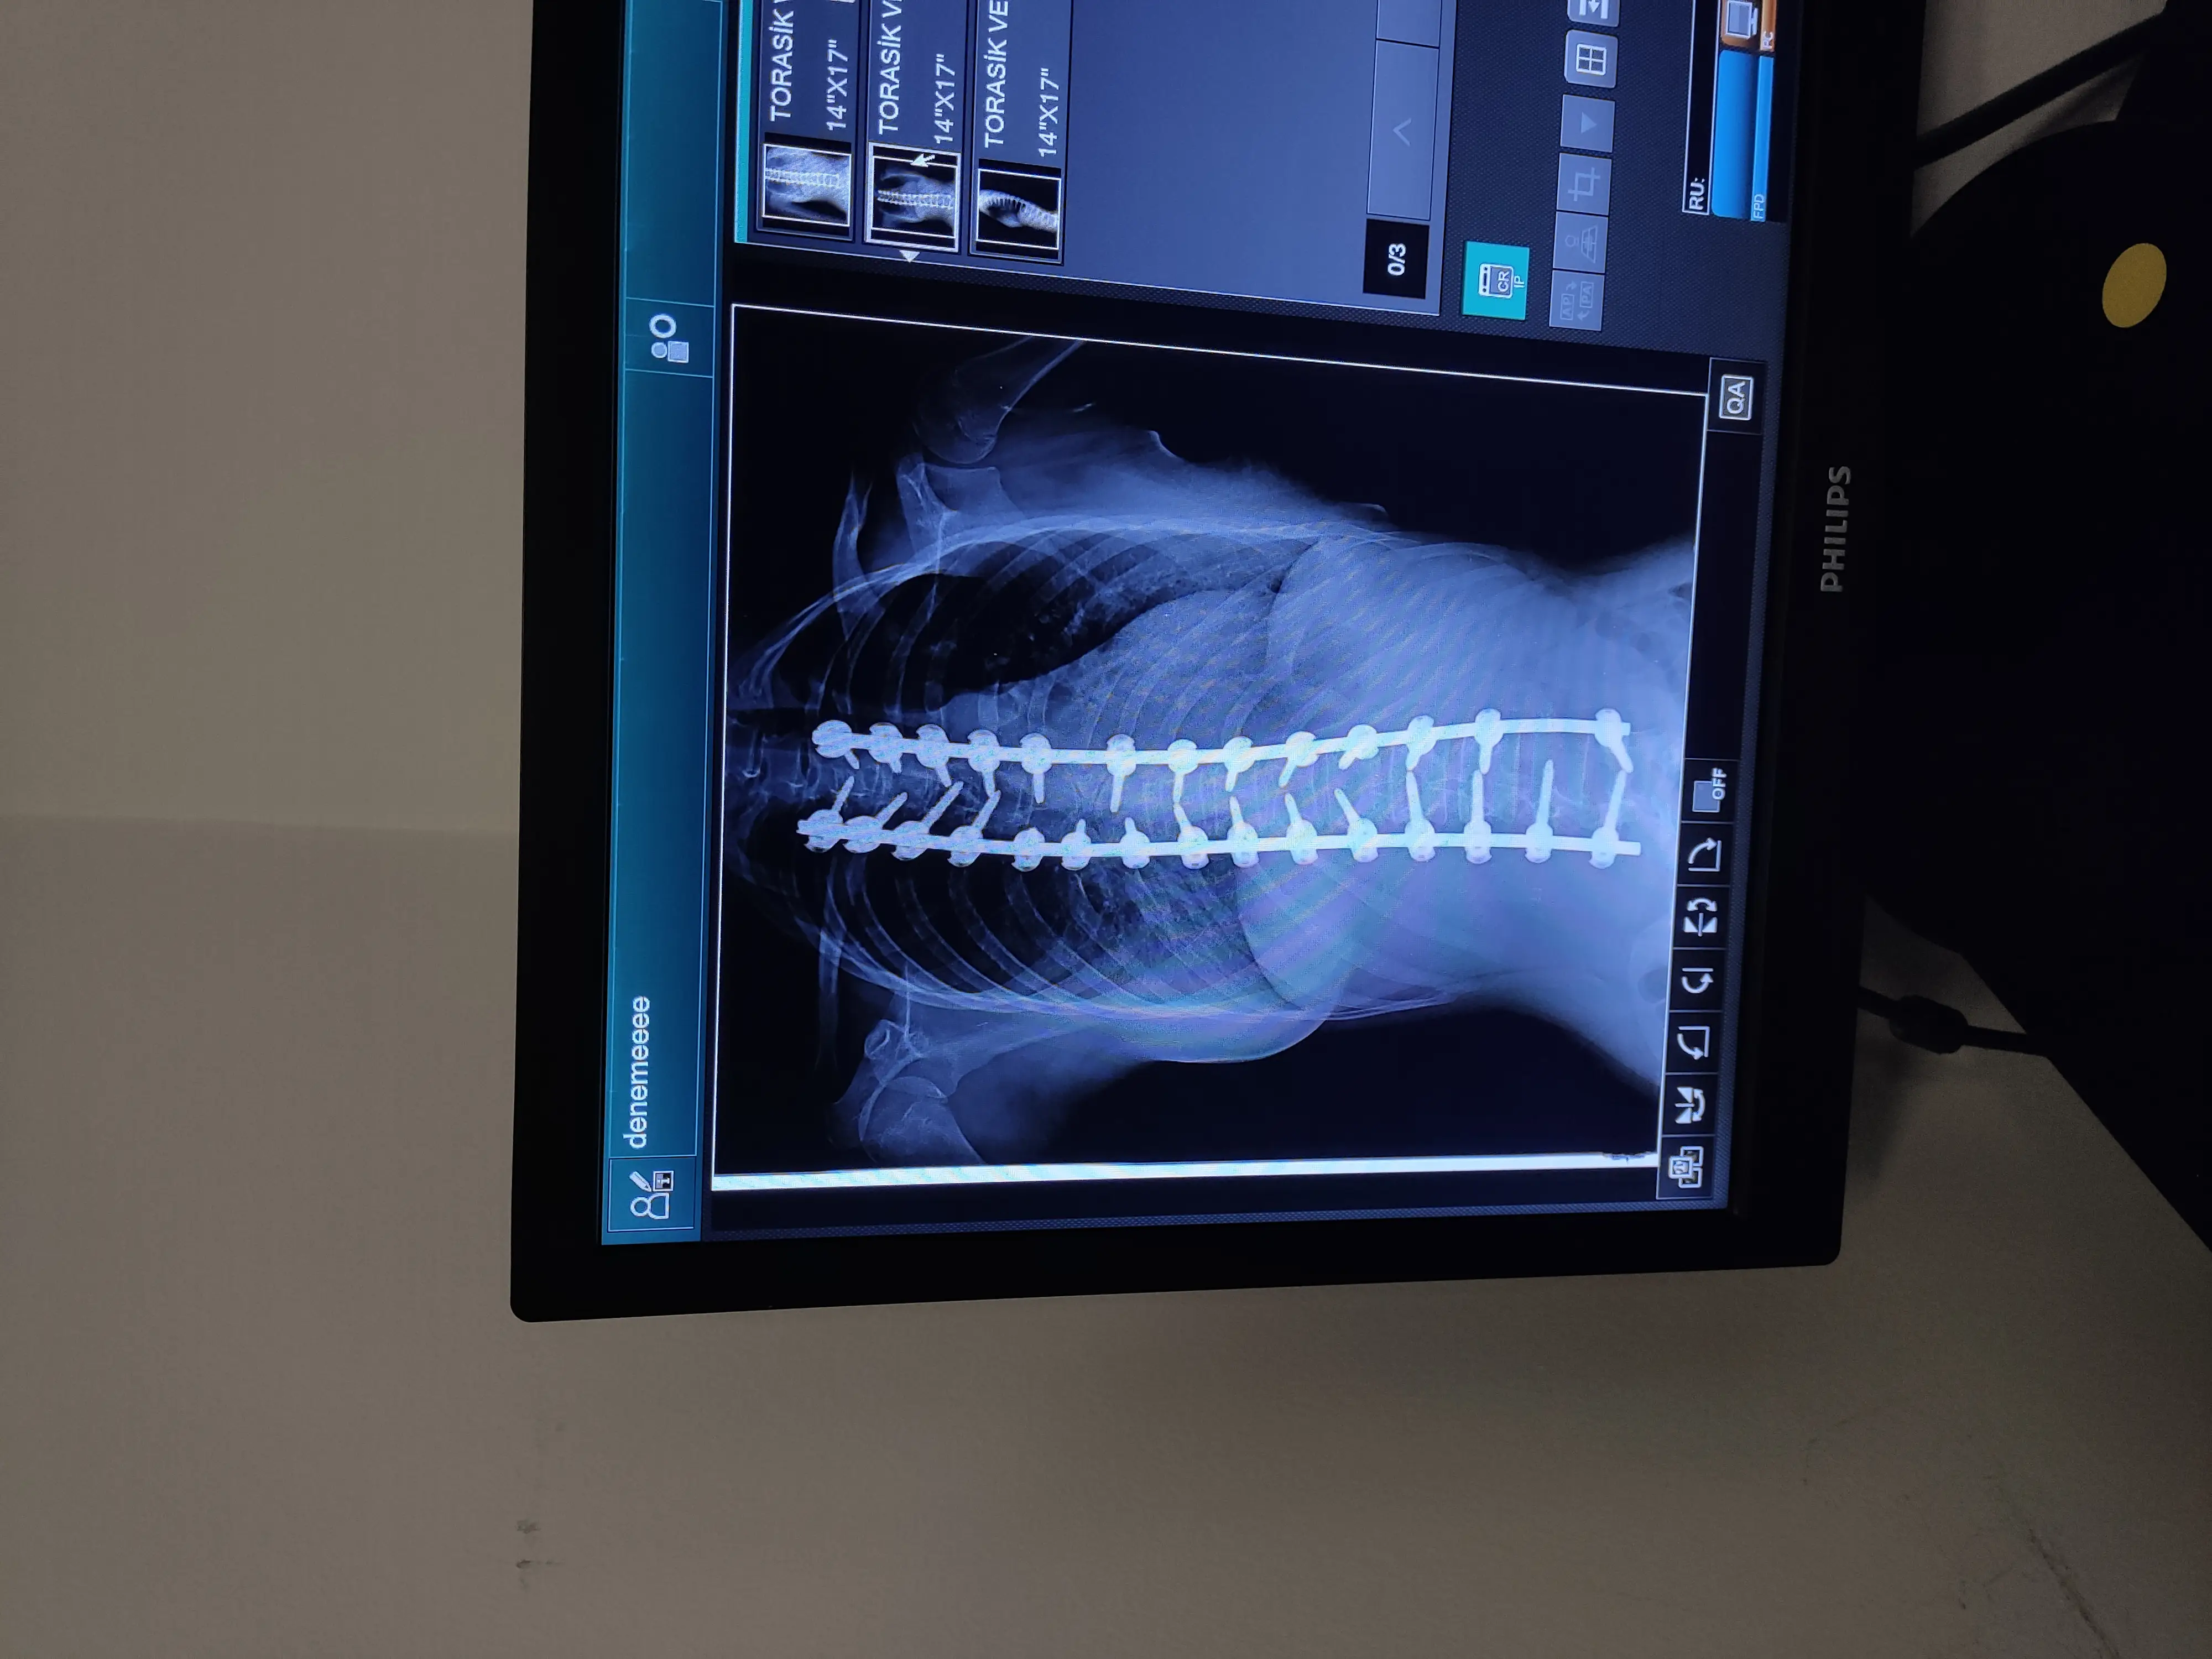

Здравейте! Нощес се прибрахме от поредните прегледи. С операцията на гръбнака всичко е наред и полека лека всичко си идва на мястото. Сърцето и белия дроб почти са заели мястото си и вече функционират добре. Лявата част на тялото и която беше силно притисната от кривата и не се развиваше, започва да наваксва изоставянето. Скъсяването на крачето още е факт, но според лекаря с развиването на крачето до някъде ще се коригира. Видимо вече има разлика с това , което беше и при раменцата. Бавно, но заемат правилната стойка. Без много навеждане, вече имаме разрешение и за четене и писане. Като цяло, лекаря каза, че първата много важна фаза от възстановяването я приключваме успешно! Терапията продължава!

Първата операция!!! Нещата са добре предвид сложността на аномалията! Не е всичко както трябва да бъде, но в нейния случай не може и да искаме повече! В началото на юни ще има нова оперативна намеса, за поредната корекция. Следваща процедура 18 април. За съжаление сумата в сметката е НЕДОСТАТЪЧНА, за предстоящите манипулации!!! Както казва Ники Кънчев, "не е нужно да даряваме хиляди, а да бъдем хиляди тези, които даряваме" ! МОЛЯ ВИ , за споделяне, за да достигне до повече хора! Нека завършим успешно борбата, за прекрасната Айси!!!

Hello! We came home from another checkup last night. All is well with the spinal surgery and slowly everything is falling into place. The heart and lung are almost back in place and functioning well now. Her left side, which was severely pinched by the curve and not developing, is starting to catch up with the abandonment. The shortening of the leg is still there, but the doctor said that as the leg develops it will correct itself somewhat. Apparently there is already a difference with what , was and the shoulder. Slowly, but taking the right posture. Without much bending, we now have permission to read and write. All in all, the doctor said that the first very important phase of the recovery we complete it successfully! Therapy continues!

First surgery!!! Things are good considering the complexity of the anomaly! Not everything is as it should be, but in her case we can't ask for more! There will be another surgery in early June for another correction. Next procedure April 18. Unfortunately the amount in the bill is INSUFFICIENT, for the upcoming manipulations!!! As Nikki Kanchev says, "we don't need to donate thousands, but to be thousands who donate" ! PLEASE , for sharing to reach more people ! Let's finish the fight successfully, for the lovely Aissy!!!